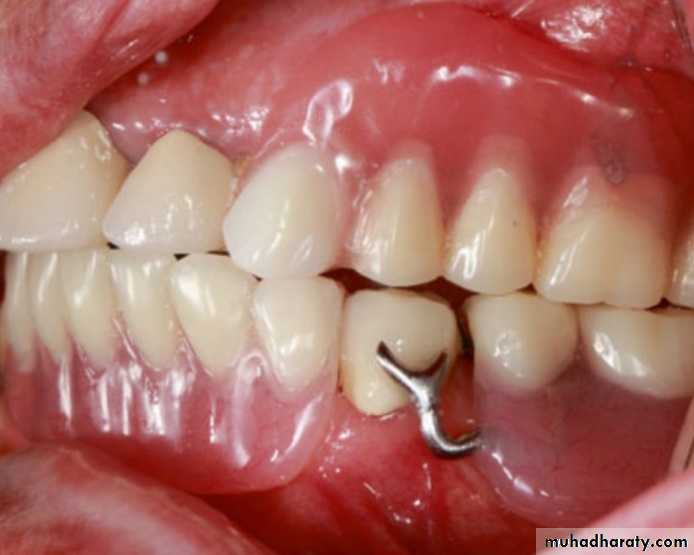

The guiding planes should be carefully examined, and if there is a minor incongruity, the RPD may seat after preparing the guiding planes.A rest and clasp assembly not fully seated will

probably apply nonaxial forces to the abutment tooth